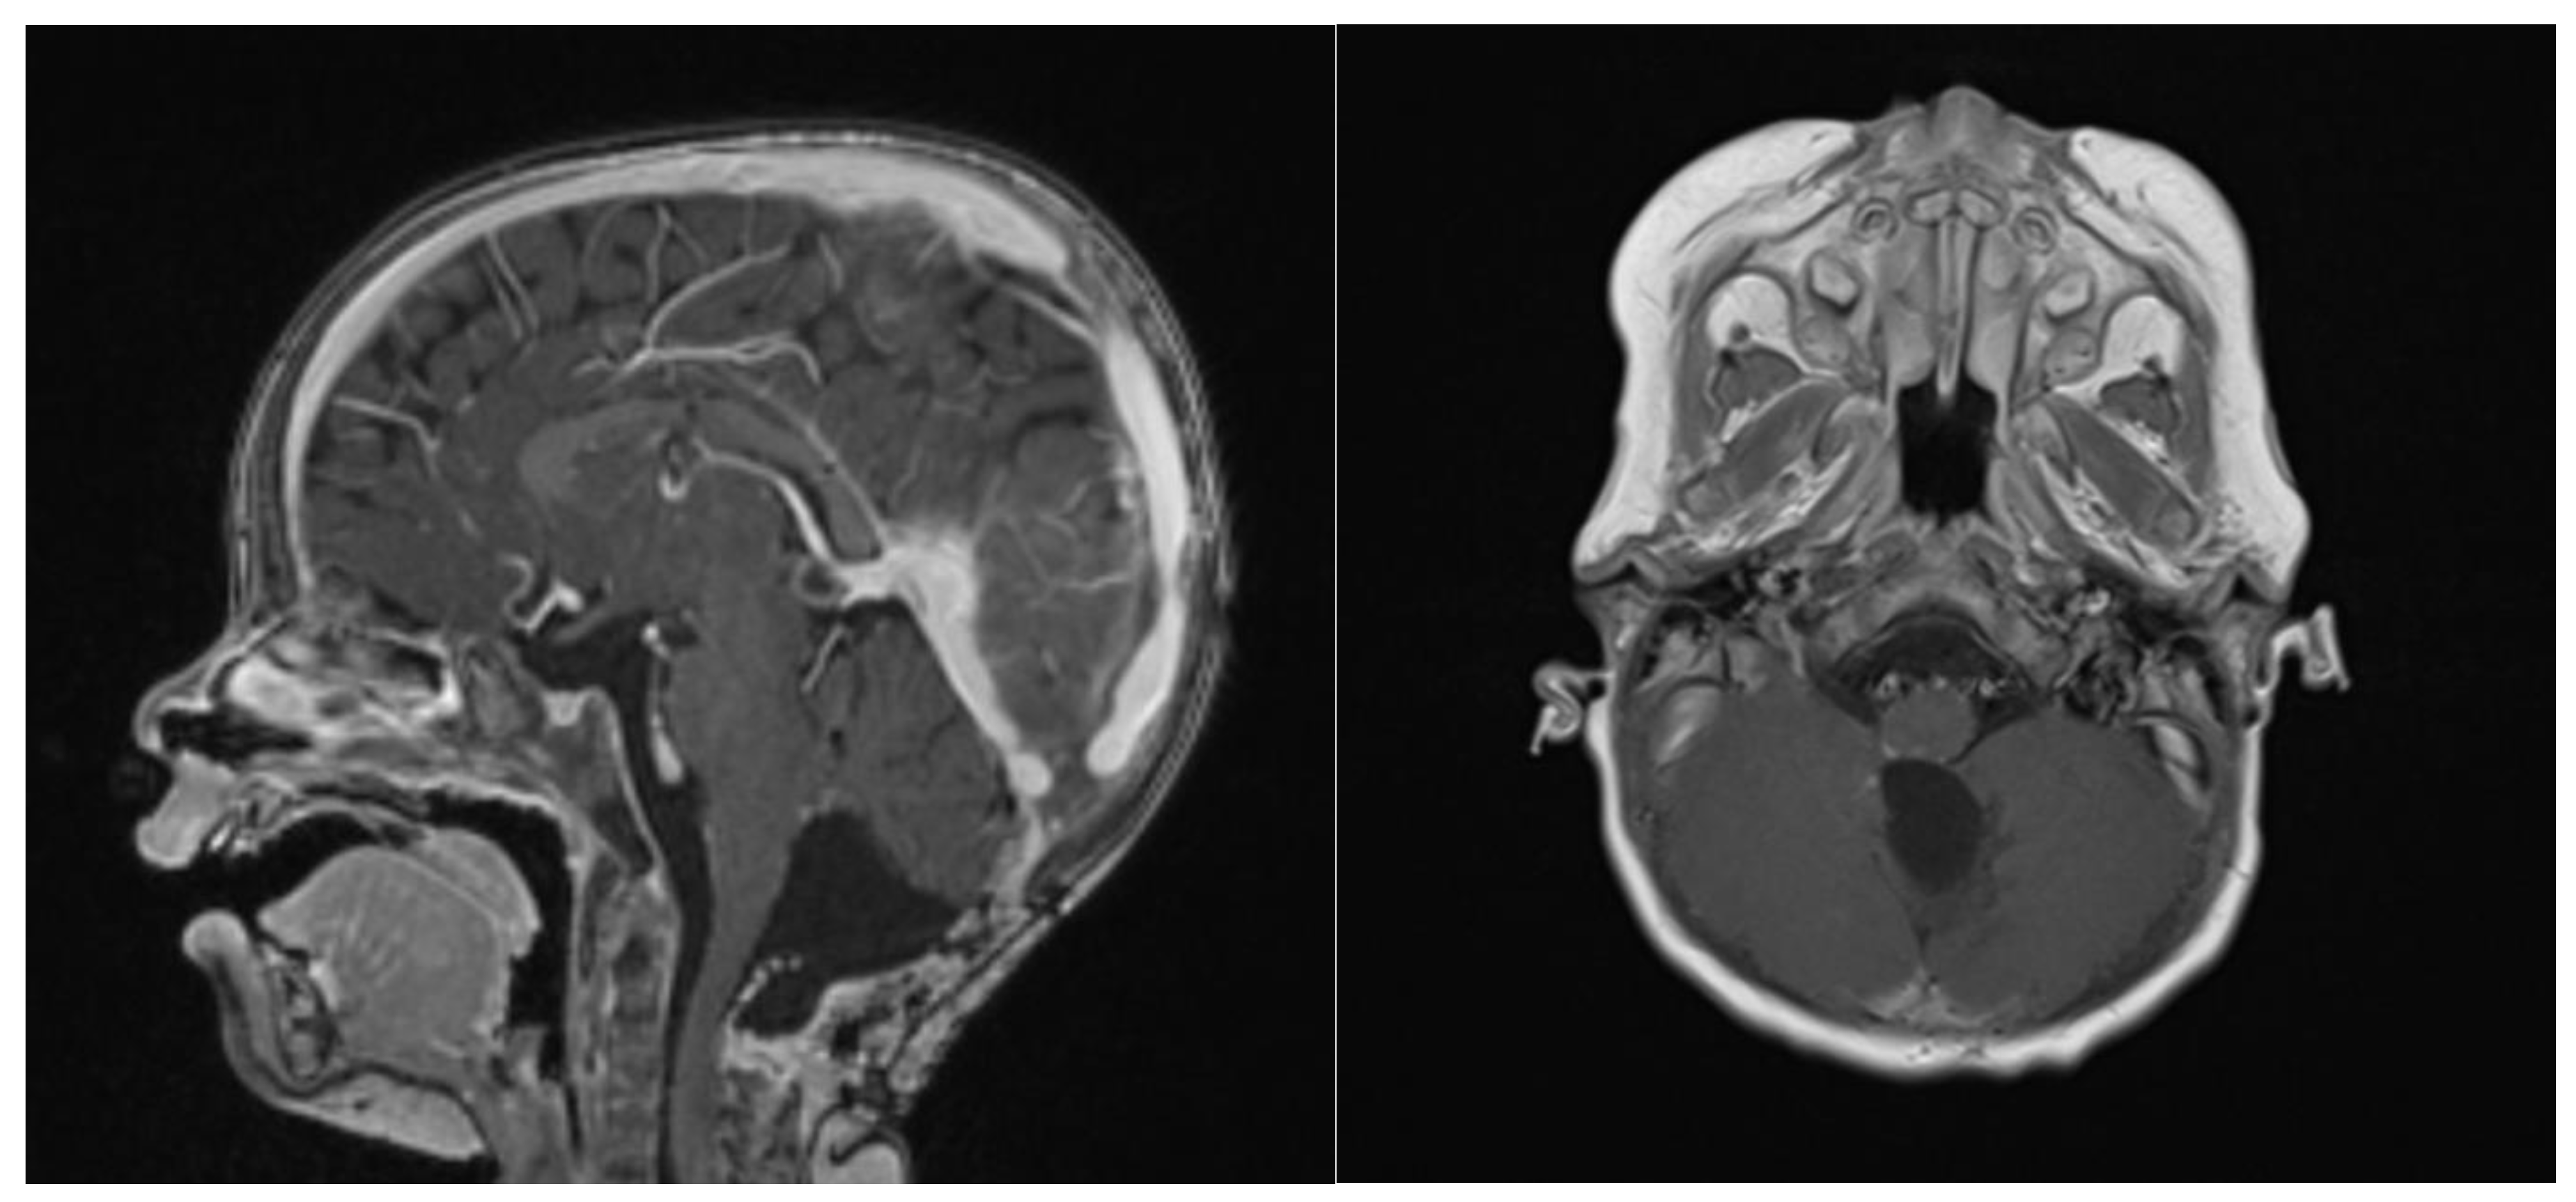

- Nowak, J.; Nemes, K.; Hohm, A.; Vandergrift, L.A.; Hasselblatt, M.; Johann, P.D.; Kool, M.; Frühwald, M.C.; Warmuth-Metz, M. Magnetic resonance imaging surrogates of molecular subgroups in atypical teratoid/rhabdoid tumor. Neuro. Oncol. 2018, 20, 1672–1679. [Google Scholar] [CrossRef]